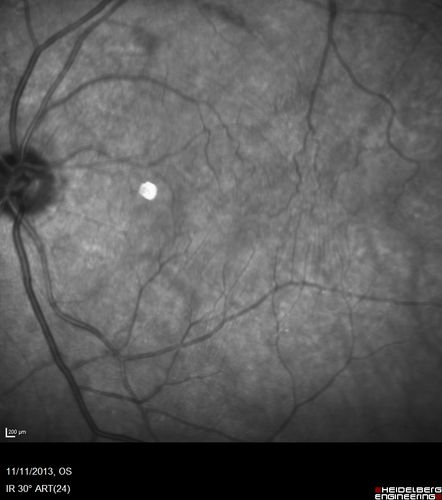

Vitreomacular Traction -> Macular Hole -> Aborted Macular hole

Progression of VMT in both eyes over time